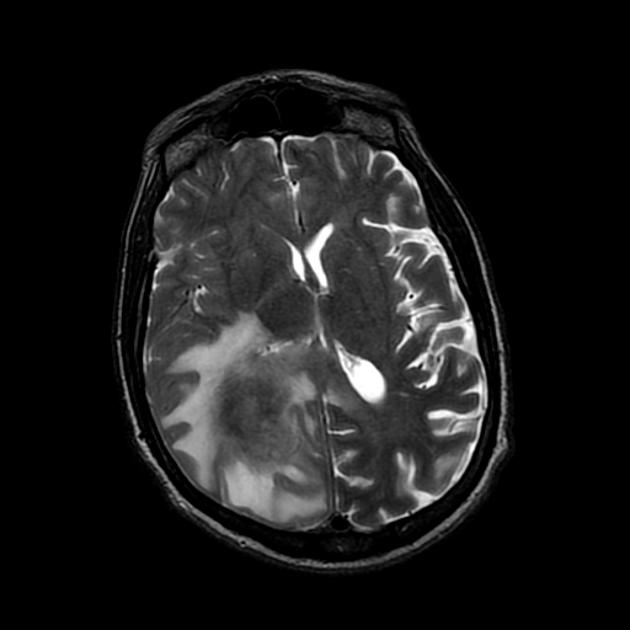

A detailed history and physical evaluation with particular attention to time course and nature of symptoms, followed by an MRI of the brain is the usual initial workup. The T1 MRI shows a hypointense or isointense lesion, and T2/FLAIR shows variable surrounding edema. T1/Gad shows homogenous enhancement without ring enhancement and lacking central necrosis. Ring enhancement occurs more often in immunocompromised patients.

CT images are hypointense. Hemorrhage is uncommon. Multiple lesions are more common in HIV+ patients.

MRI